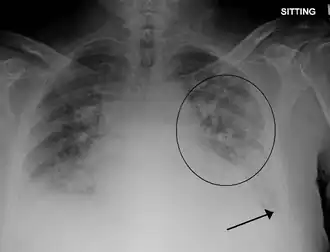

Radiografía de tórax con edema pulmonar y pequeños derrames pleurales bilaterales | ||

- Una radiografía de tórax que puede revelar líquido en o alrededor del espacio pulmonar o un agrandamiento del corazón.